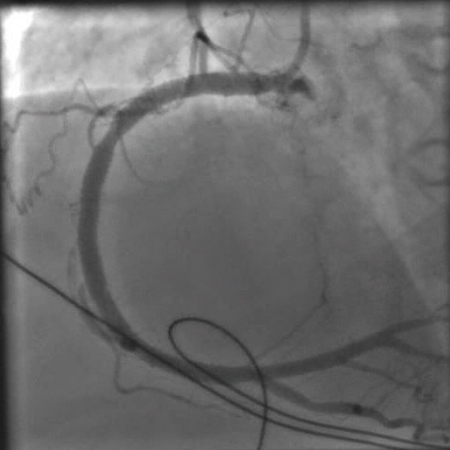

Angiografia após a angioplastia com balão e colocação de stent mostrando uma artéria coronária direita aberta

Do acervo pessoal do Dr. Mahi Ashwath; usado com permissão